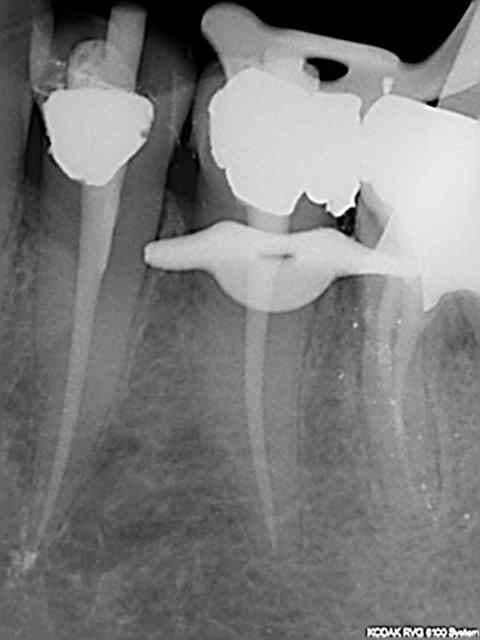

Tout frais de ce matin. T'en veux d'autres ?

R52 kxurpq - Eugenol

R46 plq0yh - Eugenol